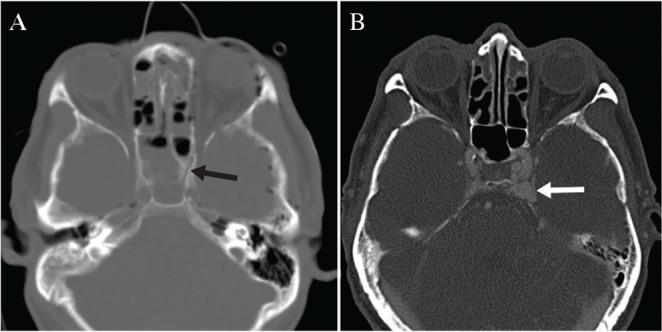

Traumatic carotid cavernous fistula (CCF) presents most commonly as a direct connection between the cavernous segment of internal carotid artery (ICA) and cavernous sinus (CS), and often accompanies basal skull fracture (BSF). The most frequently reported signs and symptoms are proptosis, chemosis, and bruit. Epistaxis is uncommon symptom of CCF. A 63-year-old man with a history of BSF due to blunt head trauma eight months previously was referred to our emergency room for massive epistaxis. Cerebral angiography demonstrated a high-flow CCF with a connection between the supraclinoid portion of left ICA and CS via a pseudoaneurysm, suggesting the life-threatening epistaxis had been caused by high-flow shunting, through the gap created by the BSF. After the complete obliteration of the pseudoaneurysm arising from the supraclinoid ICA by stent-assisted coil embolization, the CCF was no longer evident and epistaxis ceased. To the best of our knowledge, this is the first case of a traumatic CCF with a connection between the supraclinoid ICA and CS via a pseudoaneurysm, presenting with delayed life-threatening epistaxis.

创伤性颈动脉海绵窦瘘(CCF)最常见的表现是颈内动脉(ICA)海绵窦段与海绵窦(CS)之间的直接连接,且常伴有颅底骨折(BSF)。最常报道的体征和症状是眼球突出、结膜水肿和血管杂音。鼻出血是CCF的罕见症状。一名63岁男性,8个月前因钝性头部外伤有颅底骨折病史,因大量鼻出血被转诊至我院急诊室。脑血管造影显示为高流量CCF,左侧ICA鞍上部分通过假性动脉瘤与海绵窦相连,提示危及生命的鼻出血是由高流量分流通过颅底骨折造成的间隙引起的。通过支架辅助弹簧圈栓塞完全闭塞鞍上ICA产生的假性动脉瘤后,CCF不再明显,鼻出血停止。据我们所知,这是首例通过假性动脉瘤在鞍上ICA与海绵窦之间存在连接的创伤性CCF,并伴有延迟出现的危及生命的鼻出血。